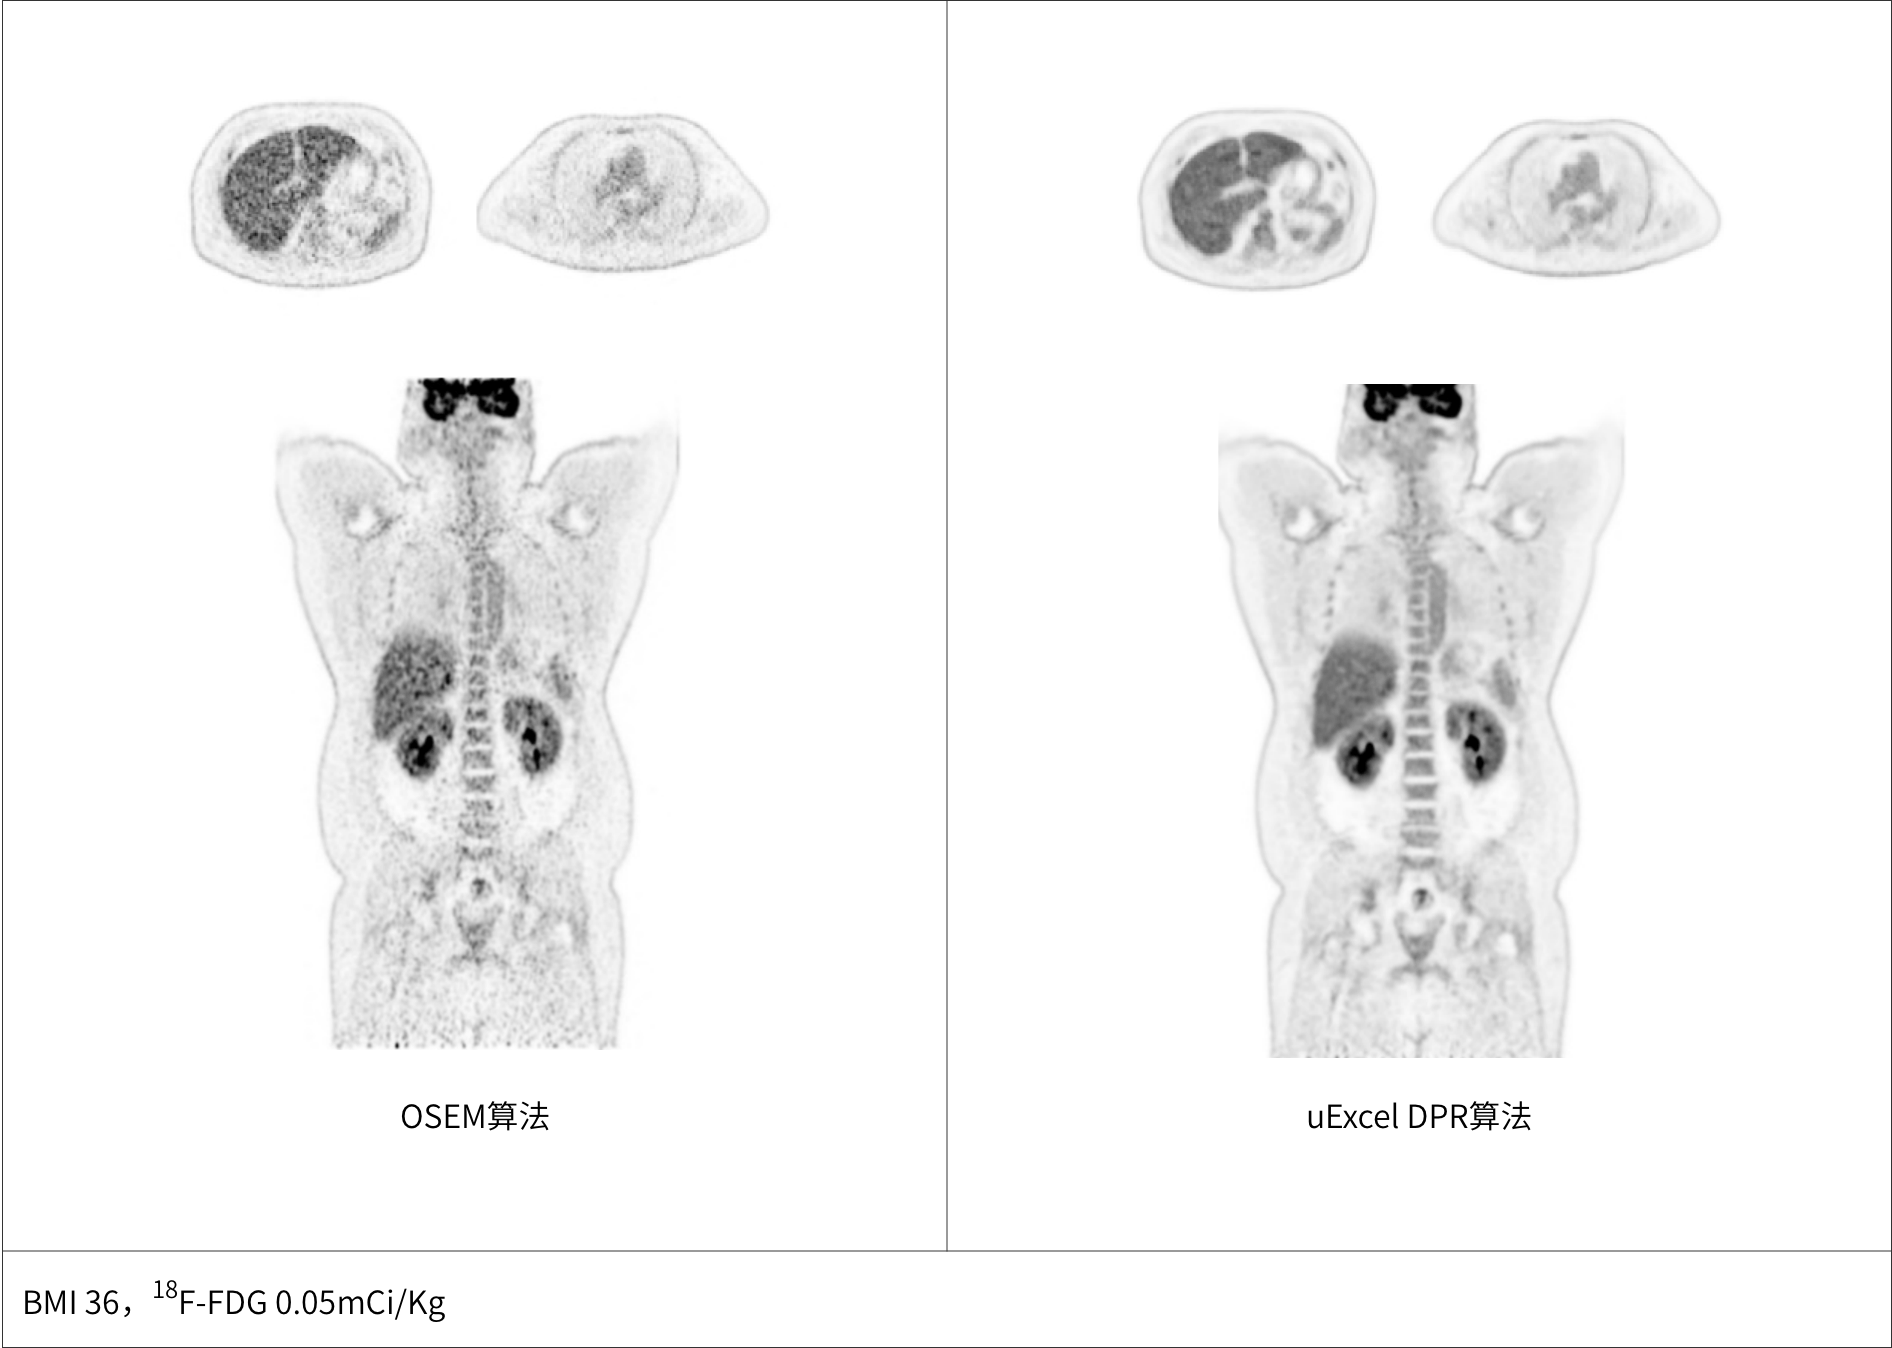

uExcel DPR*全面优化PET-CT扫描条件

兼顾噪声、对比度、分辨率等多维度进行分布渐进式学习优化

极低噪声、高对比度uEXPLORER海量优质图像训练集有效保证输出结果的可靠性

PET图像全维优化

同时实现图像对比度、噪声、信噪比三重优化

*uExcel DPR仅供科研使用